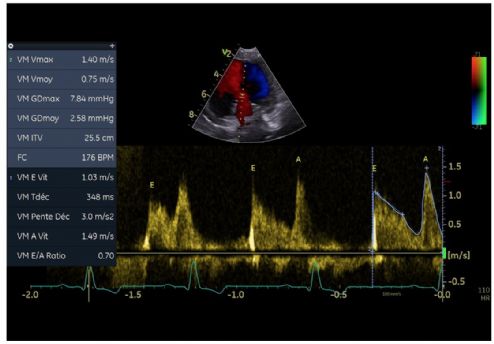

3. Au mode Doppler pulsé, une inversion des ondes mitrales et une augmentation de la valeur de l'onde A mitrale (onde E = 1,03 m/s et une onde A = 1,49 m/s ; (VU chez le chien sain onde A 0,90 m/s ; Chetboul, 2018) (Figure 11).

4. Une décroissance proto- et mésodiastolique lente de l'onde E avec un allongement du temps de demi-pression (T1/2mit) égale à 348 ms (VU 52 ms chez le chien sain selon Lehmkuhl et coll., 1994 ; Boon, 2011) (Figure 11).